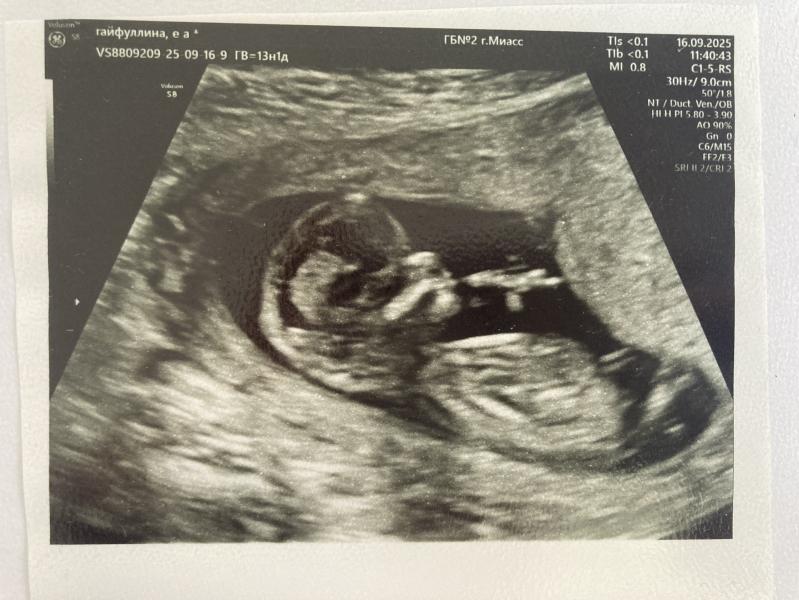

Ну вот и съездила на 1 скрининг 🙈 все хорошо ❤️